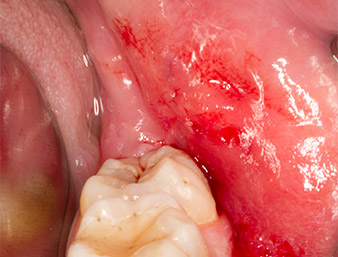

Reste radiculaire 38

Fig. 7 : Le reste radiculaire 38 (LL8) est bien exposé dans son alvéole en vue de son extraction ultérieure.